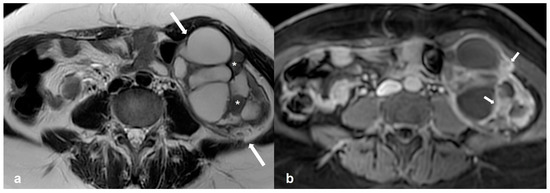

2.4.3. Dysgerminoma

- Shaaban, A.M.; Rezvani, M.; Elsayes, K.M.; Baskin, H.; Mourad, A.; Foster, B.R.; Jarboe, E.A.; Menias, C.O. Ovarian Malignant Germ Cell Tumors: Cellular Classification and Clinical and Imaging Features. RadioGraphics 2014, 34, 777–801. [Google Scholar] [CrossRef]